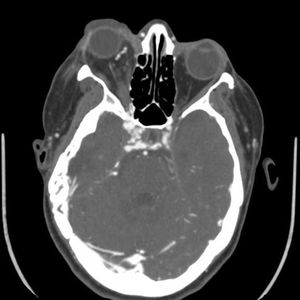

Clinical History: A 54-year-old man presented with upper lid swelling, conjunctival chemosis, and proptosis of the right eye.